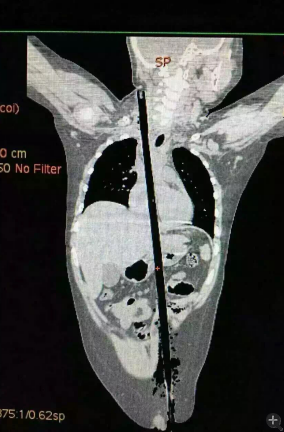

据相关知情人介绍,受伤男童24日晚在家中与小朋友一块儿在墙头上玩耍时,一不小心从高墙上跌落到了邻家花圃中,让人触目惊心的是,该男童正好跌到了花圃中的一支长约63厘米,直径约1.5厘米的竹棍上,竹棍自孩子的左侧大腿根部直接插入腹腔并入胸腔直至右侧颈部。

市儿童医院组织专家团队对孩子的病情进行检查、评估后发现,竹棍由患儿左侧大腿根部插入,经腹腔穿透胃、肝脏、膈肌入胸腔,并穿透患儿心脏,经胸腔入颈部,此刻不能拔除竹棍,因为去除竹棍会导致心脏、肝脏破裂大出血导致休克,危及性命。

由于竹棍自心脏的右心房膈面穿入心脏,并由右房近左房顶处穿出心脏,经右胸顶刺入右颈部,右心房破口处紧邻右冠状动脉,幸运的是胸腔内大血管无损伤,在体外循环辅助下,医护团队异物穿出处锯断异物,将插入心脏内的竹棍截断拔除,修补心脏破损处,向上继续寻找周围组织的游离异物,见异物紧临颈部大血管,经精细手术,终于抽出了异物。整个手术时间花了十多个小时。